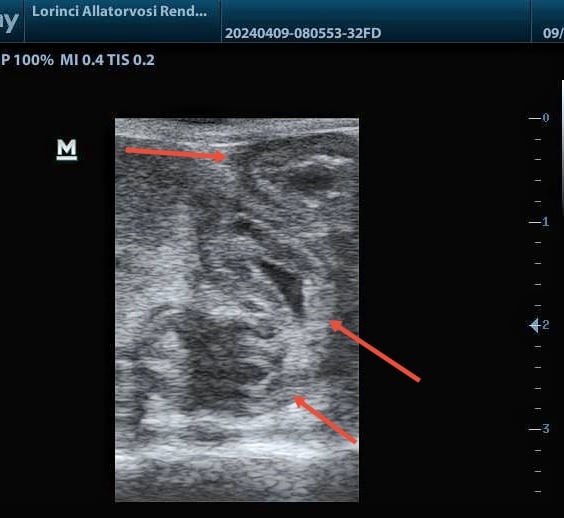

Az IBD és a limfóma érintheti diffúzan a beleket és/vagy a gyomrot, ilyenkor a tápcsatorna szerkezete hosszabb vagy több szakaszon mutat elváltozást. A falszerkezet sokszor felismerhető marad, de a különböző rétegek abnormális megvastagodása detektálható.

Gyűrűszerűen megvastagodott vékonybél